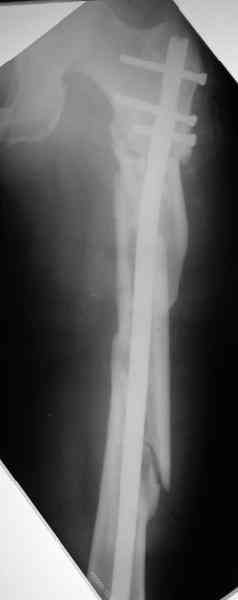

Уважаемые коллеги! Пришел на консультацию вот такой больной (первые 3-и рисунка). Травма автодорожная, апрель 2006г. Лечился консервативно, вытяжение и гипс. Через пять месяцев стал ходить. Укорочение бедра 6 см. 26 февраля 2007г. оступился, упал. Прооперирован в г.Баку - наложен стержневой аппарат. Ходит с костылями, наступая на левую ногу. Мы попросили что нибудь из ранних снимков. Принес рентгенограммы перелома (рис. 4,5). Посмотрели, наснимали сами (рис. 6-10). Похоже, что нет сращения нигде. Хотелось - бы обсудить следующие вопросы:1. дальнейшая тактика - реостеосинтез или подождать (ослабить аппарат, дать нагрузку и т.д.)?2. если реостеосинтез - то чем и как? Юрий Алексеевич Булахтин

Лучше бы закрытый интрамедуллярный, конечно.

Надо делать чрескожную подвертельную остеотомию, чтобы получился открытый клин. Проблемы будут и с формированием канала, надо развертки типа наших. Был как-то похожий случай, сделали одномоментно, сняли аппарат 5-месячый на столе, заштифтовали с подвертельной остеотомией (в приложении).

Можно все коррекции сделать и в аппарате, и потом заштифтовать, тогда останется только одна проблема формирования канала.

Если только аппарат стабилен, мне кажется, можно продолжить стабилизацию. При таком сложном переломе важно достичь консолидации в области диафиза. Варус в подвертельной области можно откоррегировать позже. Есло позволяет конструкция внешней опоры и позволяет состояние мягких тканей - усилить базу в проксимальном фрагменте и попытаться устранить деформацию в процессе, хотя это маловероятно. желаю успеха. Анатолий